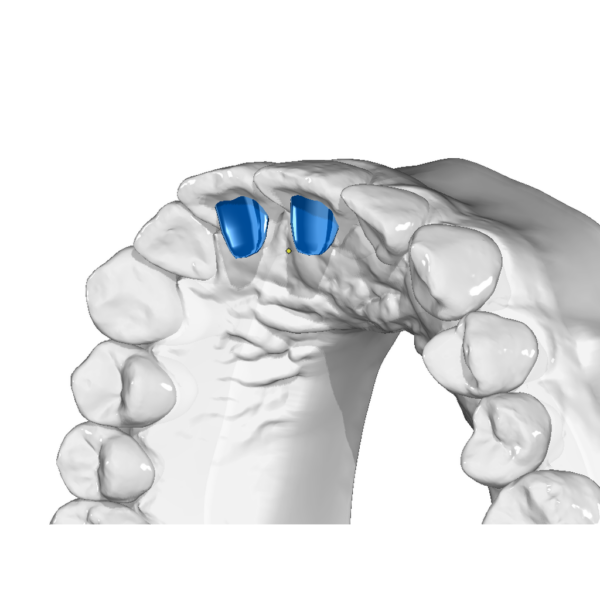

Aligner Accessories (STL Templates for Enhanced Aligner Therapy)

Clear aligners are powerful—but with the right accessories, they become truly versatile. This category offers STL templates for attachments and add-ons that enhance biomechanics, giving orthodontists greater control and precision in aligner therapy.

✔ Digital workflow ready: all templates provided as STL files for seamless integration